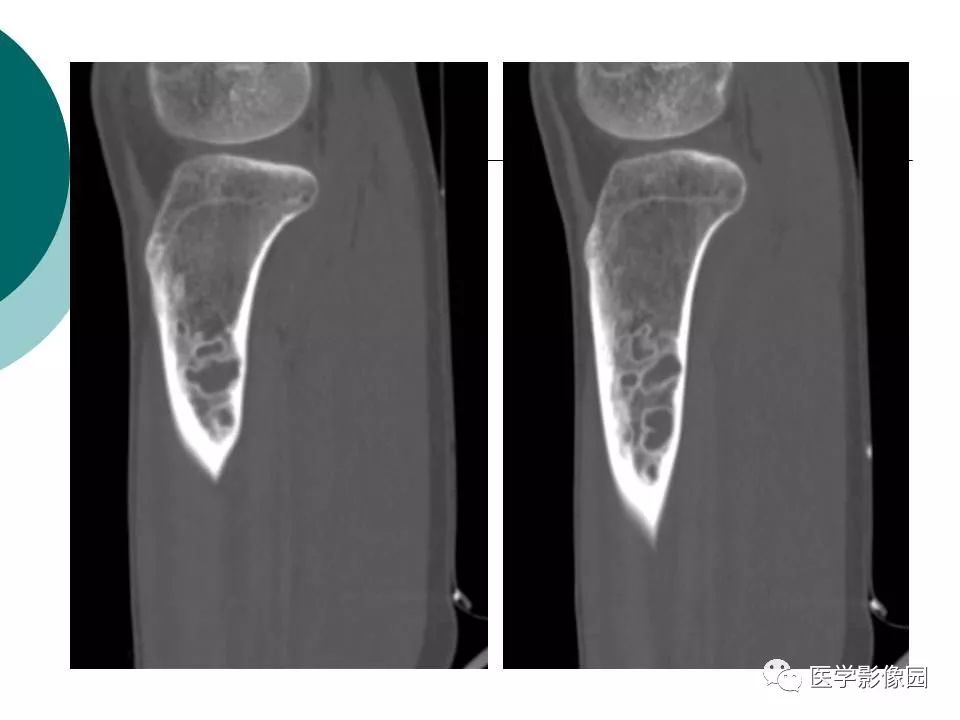

【病例】胫骨非骨化性纤维瘤1例CT及MR